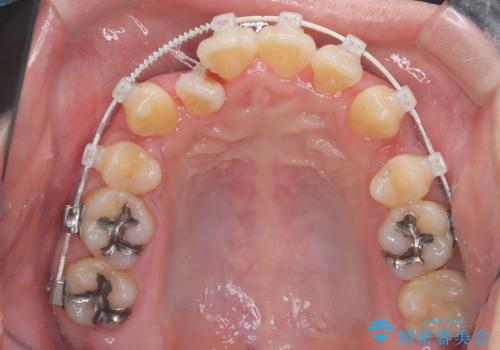

- 「歯のデコボコと前歯が引っ込んでいるのを治したい」を主訴に来院された患者様です。

デコボコの量が多かったため上下左右4を抜歯してワイヤー矯正で治療を行いました。

正面から見たときに右上2が全く見えないくらい、右上2が後ろに引っ込んでいる状態でしたが綺麗に並べる事が出来ました。